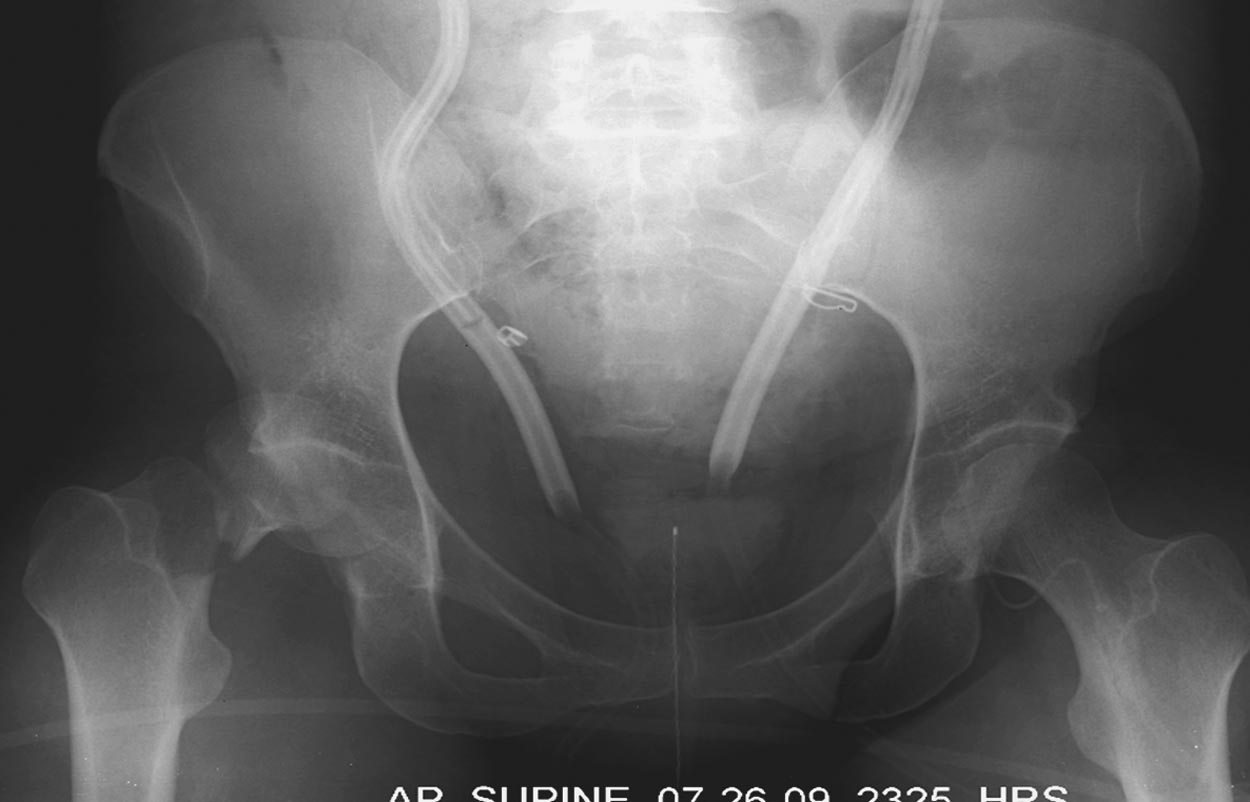

Вложение не в текстовом формате было извлечено…

Имя     : Picture4.jpg

Тип     : image/jpeg

Размер  : 25810 байтов

Описание: отсутствует

Url     : http://weborto.net:8080/pipermail/ortho/attachments/20180407/cb9d5034/attachment-0013.jpg